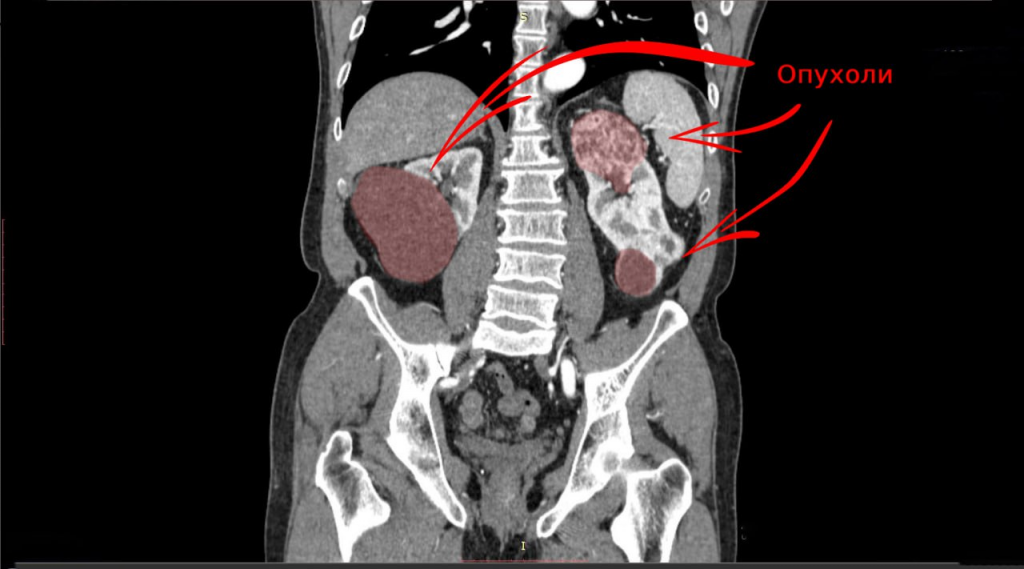

Врачи отделения онкоурологии Свердловского областного онкологического диспансера спасли пациента, у которого обе почки были поражены объёмными злокачественными новообразованиями. Такой синхронный рак встречается редко — лишь в 2-6% случаев. Чтобы сохранить пациенту жизнь и дать ему шанс избежать постоянного гемодиализа, медики успешно выполнили два сложнейших хирургических вмешательства.

Наличие новообразования у свердловчанина заподозрил врач первичного звена системы здравоохранения в ходе планового медосмотра. Мужчину направили для углублённого обследования в Свердловский областной онкодиспансер, где врачи установили, что опухоль в правой почке диаметром более шести сантиметров распространилась почти на 50% паренхимы — важнейшего элемента почечной ткани. Орган удалили, его функции взяла на себя левая почка, но и она была поражена опухолью. Чтобы максимально радикально удалить рак, при этом сохранив жизненно важную функцию почки, онкологи выполнили ещё одну операцию.

«Два новообразования в оставшейся левой почке располагались в верхнем и нижнем сегменте. Это давало возможность сохранить 70% почечной ткани. Удаление опухолей суммарным размером 12 сантиметров выполнили успешно, с минимально короткой ишемией (необходимым снижением притока крови к органу) в 12 минут», — пояснил хирург отделения онкоурологии СООД Александр Орлов.